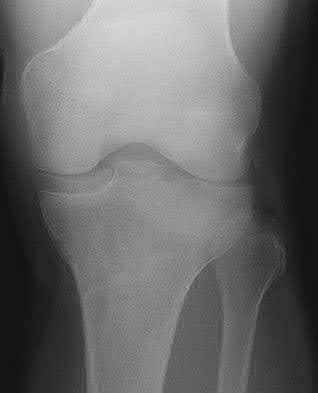

2. # A 35-year-old woman is involved in a head-on collision while driving. Initial radiographs are shown in Figures 8a and 8b. Injury to what vessel increases the risk for osteonecrosis of the injured bone?

1. Dorsalis pedis artery

2. Perforating peroneal artery

3. Lateral tarsal artery

4. Artery of the tarsal canal

5. Artery of the tarsal sinus Corrent answer: 4

The patient has a Hawkins type III talar neck fracture-dislocation with a risk of osteonecrosis ranging from 69% to 100%. Anatomic studies have shown that the artery of the tarsal canal supplies the lateral two thirds of the talar body.

The other vessels listed provide no significant contribution to the talus.